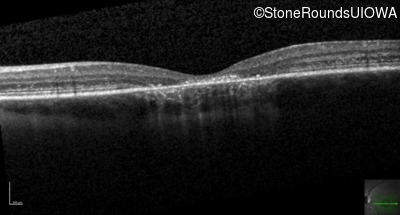

Optical Coherence Tomography - Right - 20/160 +2 sc

Exemplar / OCT Stack